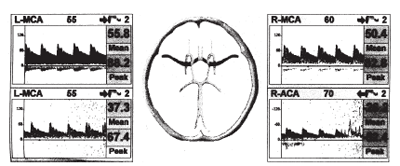

Данные допплерографического исследования. По данным ТКД каких- либо специфических паттернов мозгового кровотока не отмечается, скоростные показатели, индексы периферического сопротивления находятся в пределах возрастной нормы, т.е. имеется магистральный тип потока, иногда с незначимой асимметрией. Каких либо значимых нарушений реактивности при проведении функциональных тестов не отмечается (рис.1,2).

Рис.1

Рис.2